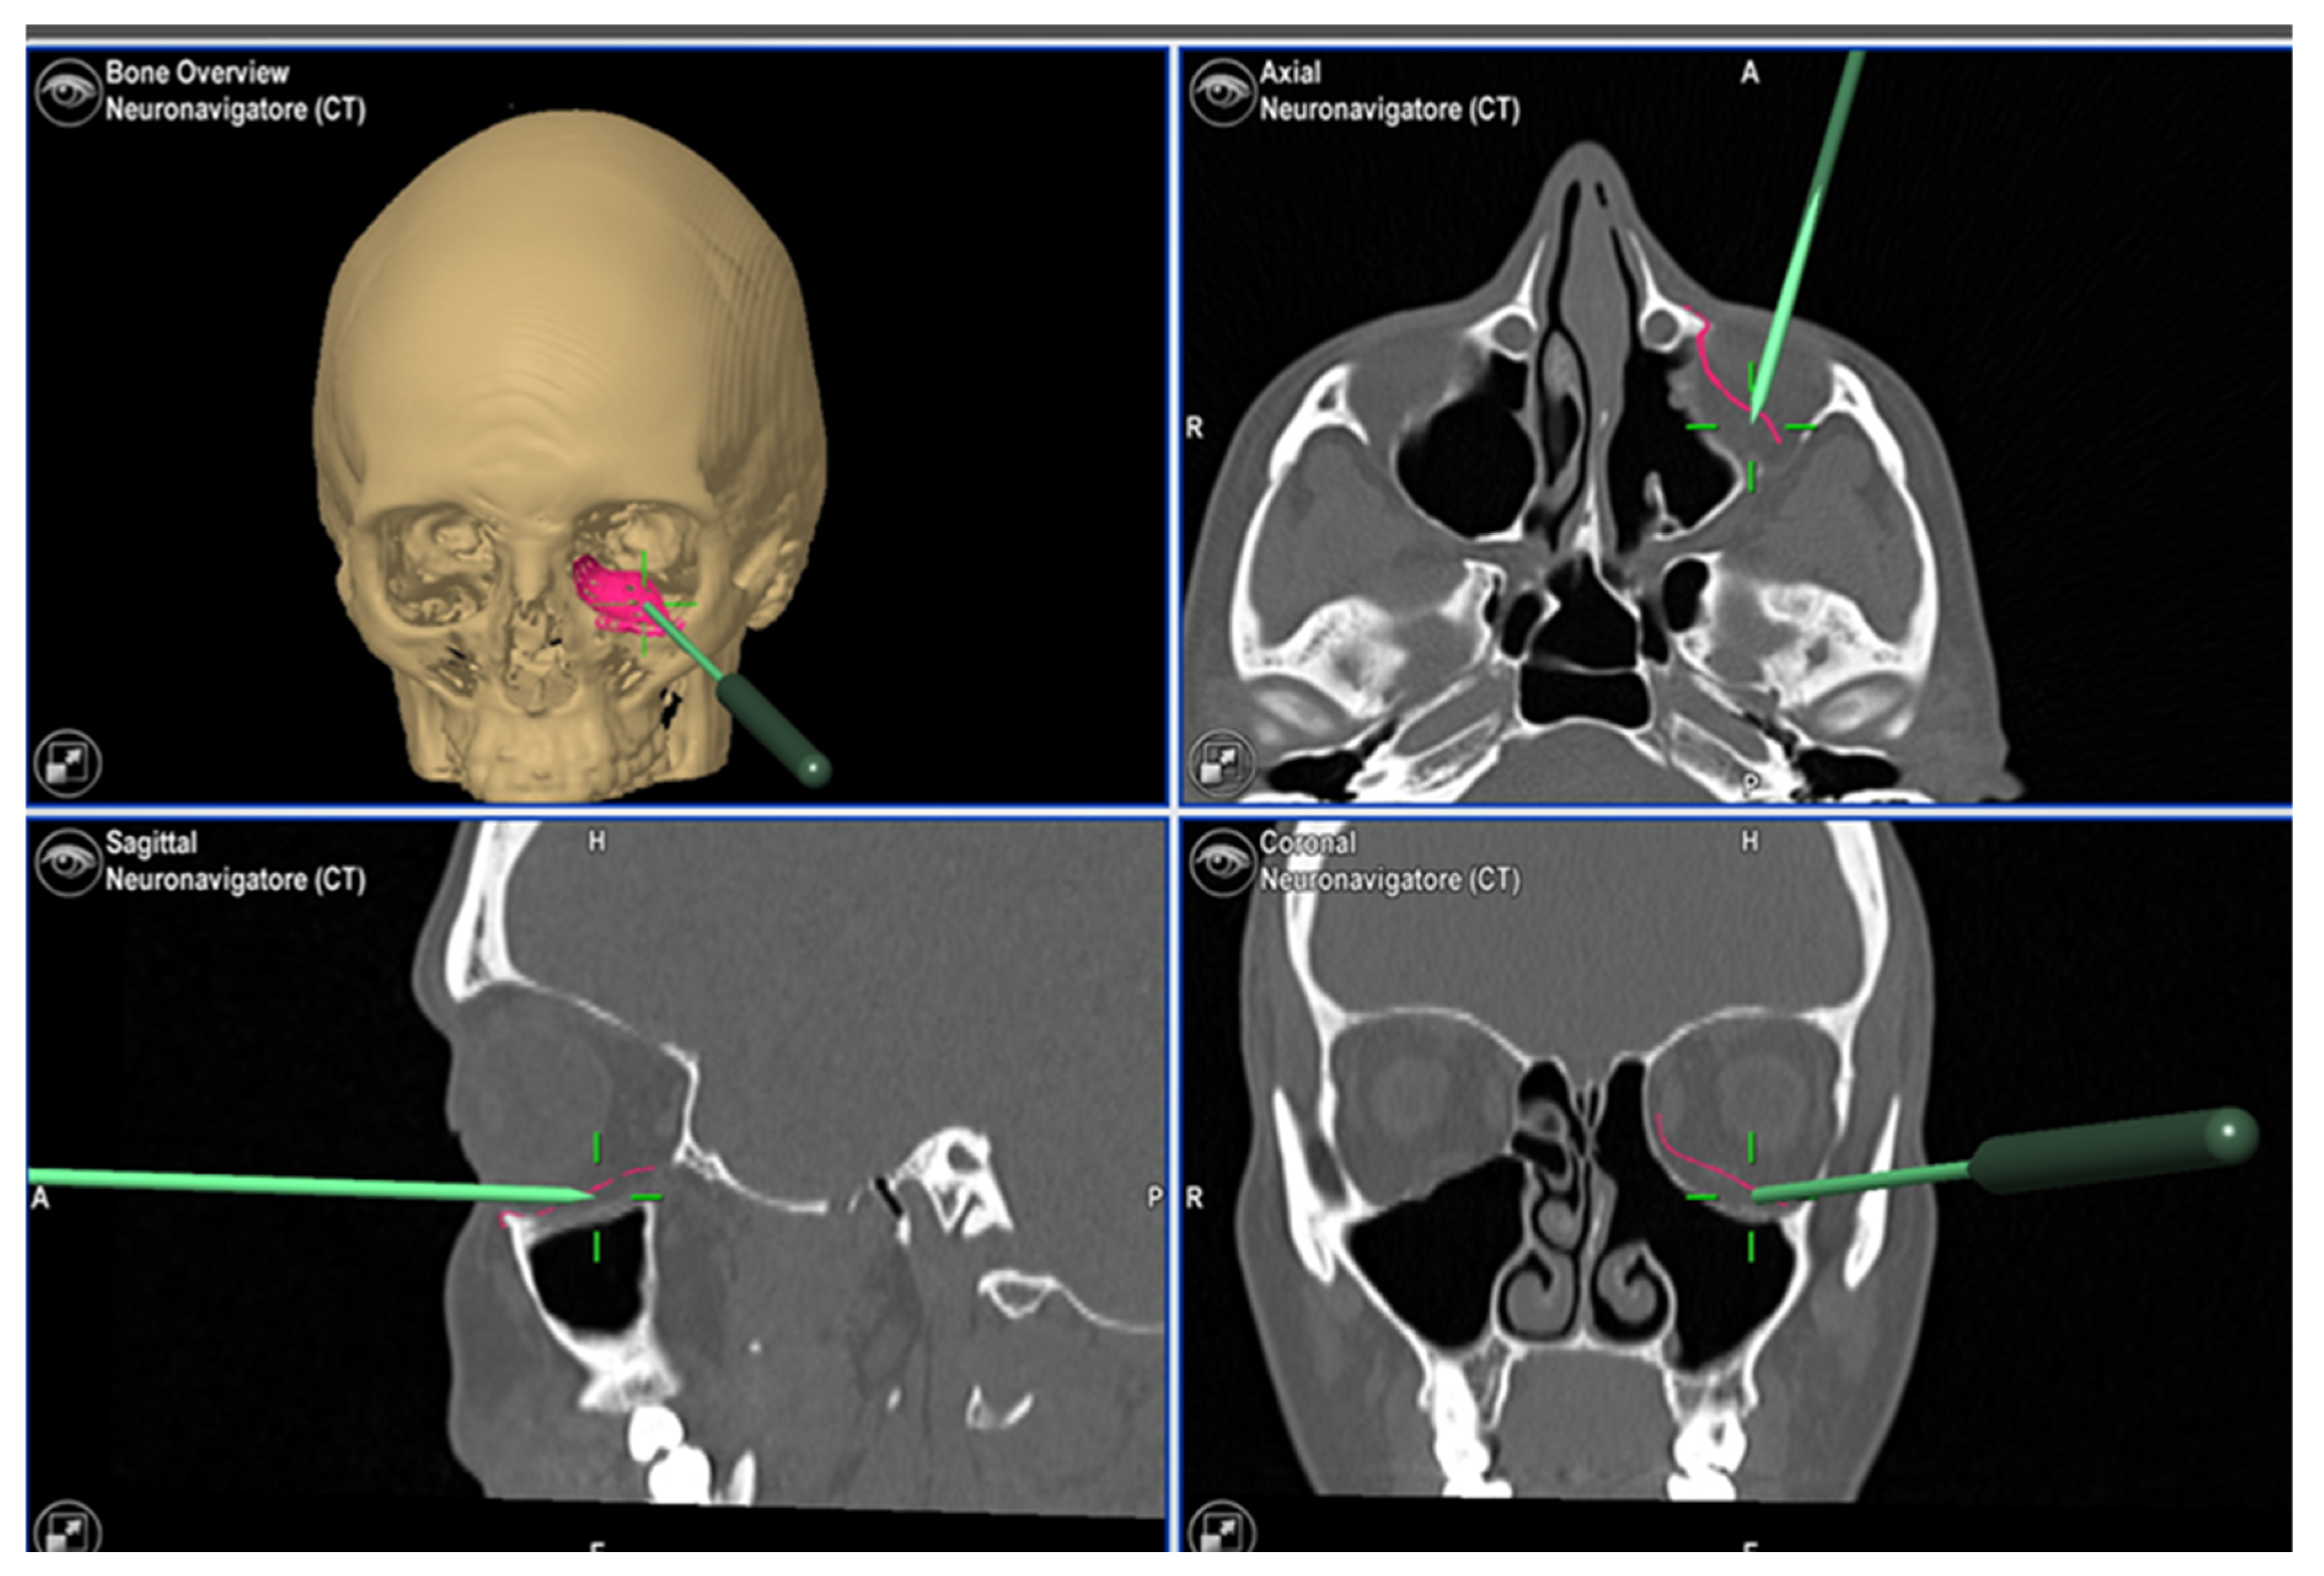

2. Case Report 1